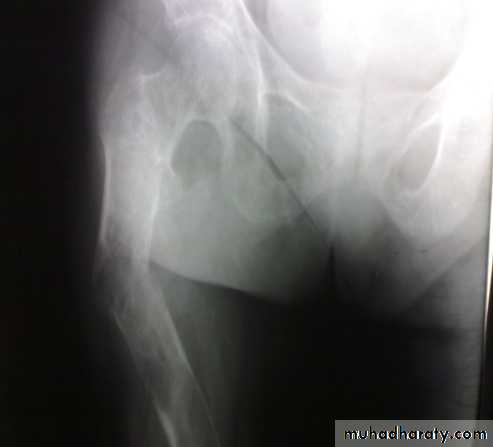

X-ray:

Usually there is some comminution.

X-ray of the pelvis and the knee to avoid missing injuries.

Intramedullary nail with interlocking screws is the method of choice